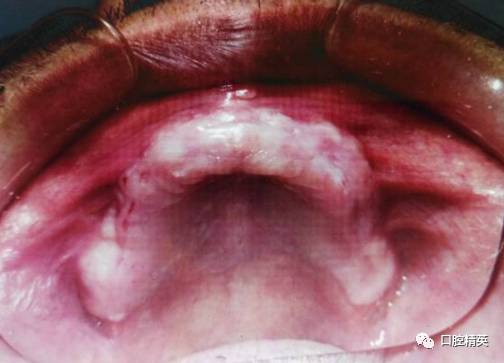

上颌牙槽骨较丰满,牙槽嵴粘膜轻度红肿及义齿摩擦损伤。无尖锐骨尖,无松软牙槽嵴。

上颌旧义齿检查:张口说话咀嚼义齿脱位,无吸附力,上颌前牙过度唇倾,覆盖较深,颌平面低于上唇缘,微笑不露义齿,口角下垂,面部下1/3欠丰满。腭盖为金属基托,义齿后部未达腭小凹后2mm处。下颌金属支架义齿,33牙缺失。